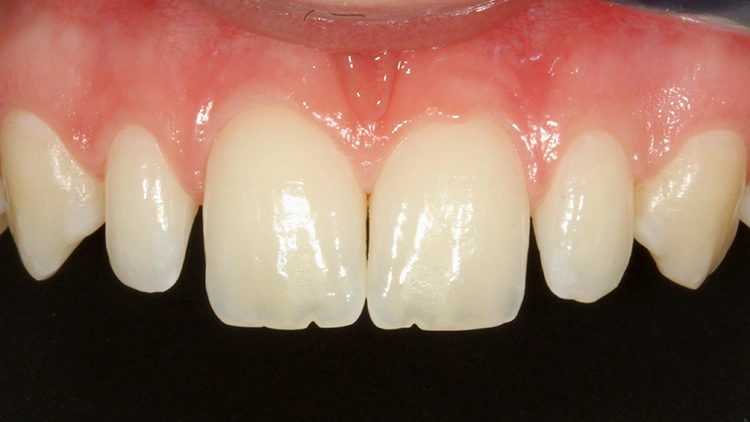

Das Endergebnis (Abb. 21 bis 24) entsprach exakt den Wünschen der Patientin, wobei aus Sicht des Autors der Zahn 12 durchaus durch das Einlegen aufhellender Malfarben ästhetisch hätte gewinnen können. So zeigt jeder Fall immer ein Verbesserungspotenzial für den nächsten Fall auf. Die individuelle Lernkurve endet nie. Prof. Dr. Ernst

In den Abbildungen 21 und 23 fallen die aus Sicht des Autors nicht mehr vollständig suffizienten mesialen Anbauten an den beiden mittleren Schneidezähnen auf. Darauf wurde die Patientin bereits im 1. Beratungsgespräch aufmerksam gemacht. Ihr war durchaus bewusst, dass diese Anbauten demnächst auch ausgebessert oder erneuert werden müssten, sie wollte damit allerdings noch ein paar Jahre warten.